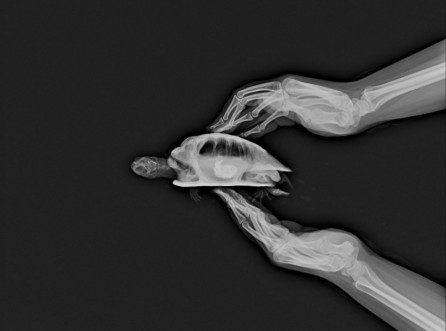

거북이, 이물섭취